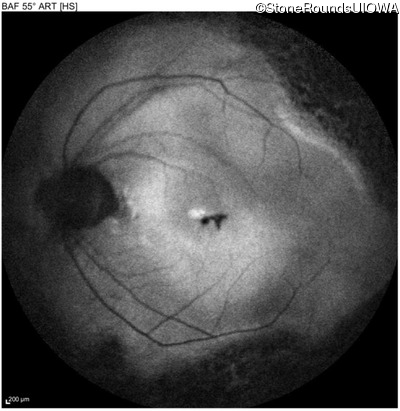

Age at visit: 47 years

OD OS

This 47 year old woman began wearing glasses at age 5 and had cataract surgery at age 32. At that time her doctor noticed a retinal abnormality.